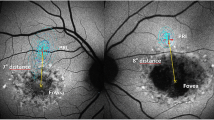

Patients underwent a comprehensive ophthalmological examination including measurement of best-corrected visual acuity (BCVA), assessment of intraocular pressure via Goldmann applanation tonometry, fundus examination, fundus autofluorescence imaging, and macular SD-OCT (version 1.5.12.0, Heidelberg Spectralis, Heidelberg Engineering, Inc., Germany). It has a 3.9-μm axial resolution and scans at 40,000 A-scans per second. For the peripapillary RNFL measurements, the RNFL exam protocol was used for scan acquisition, which was measured automatically by the existing software at a diameter of 3.45 mm around the centre of the optic disc after dilation of the pupil with 1% tropicamide. OCT analysis was performed in accordance with the APOSTEL recommendations for reporting quantitative optical coherence tomography studies [23]. All measurements were performed between 8 and 11 a.m. The same device was used for each patient. Since only high-quality pictures were included, there was no flawed segmentation of the peripapillary RNFL thickness measurements and therefore manual correction was not necessary. The global (G), temporal-inferior (TI, 270 to 315°), temporal (T, 315 to 45°), temporal-superior (TS, 45 to 90°), nasal-superior (NS, 90 to 135°), nasal (N, 135 to 225°), and nasal-inferior (NI, 225 to 270°) RNFL thickness measurements were recorded separately for each sector in micrometres (μm; Fig. 1). The pie charts in Fig. 1 are colour-coded according to percentiles as defined by the manufacturer leading to the following sector classifications: A green sector represents the area above the 5th percentile of the RNFL thickness distribution of eyes in the reference database (within normal limits). A yellow sector represents the area below the 5th percentile, but above the 1st percentile (borderline). A red sector represents the area below the 1st percentile (outside normal limits). The normative data provided by the manufacturer of the OCT device includes 201 healthy Caucasian patients (90/111 females/males) with a mean age of 48.2 ± 14.5 years (range 18 to 78 years) and a refractive error not exceeding + 5 or − 7 D sphere. Peripapillary RNFL thickness decreases slightly with age in healthy patients [24]. The reference database is therefore adapted to the age in order to take this tendency into account. In addition to the colour-coding, the pie charts illustrate the measured RNFL thickness of each sector (black numbers) compared to the age-correlated 50% percentile (green numbers). This age-correlated 50% percentile is calculated individually for each patient by the manufacturer software using the normative database described above. In Fig. 1B‴, for example, the measured RNFL thickness of 61 μm in the temporal sector (black number) is 16 μm thinner—defined in the following as “difference of peripapillary RNFL thickness”—than the age-correlated 50% percentile (77 μm, green number).

Incorrect peripapillary RNFL thickness measurement due to misalignment to the fovea. Data of an exemplary patient (ID4, see Table 1) are shown. (A) Incorrect measurement results of the peripapillary RNFL thickness due to an incorrect detection of the fovea, resulting in an incorrect thin peripapillary RNFL outside normal limits in the temporal-inferior area (A‴). (B) After manual correction of the optic disc-fovea angle (red arrow, B), the peripapillary RNFL thickness measurement was rotated by a corresponding number of degrees compared to the reference database (in the direction of the red arrows, B″), which resulted in measured normal RNFL thickness in the temporal-inferior area (B‴) and a measured thinner RNFL thickness of the temporal quadrant from 77 μm (A‴) to 61 μm (B‴). The age-correlated 50% percentiles of each sector, which are calculated individually for each patient by the manufacturer software using the normative database described in “Methods,” are illustrated in green numbers

If the fovea was not detected correctly by the Heidelberg Eye explorer software, the optic disc-fovea angle (ODFA) was manually corrected as described in Fig. 1 by the grader MR.

Correction of the optic disc-fovea angle

Automatic software detection of the fovea failed in 15 eyes (38.5%) of 11 patients (55%). In these eyes the ODFA was corrected manually. The mean corrected angle between the fovea and the optic nerve centre relative to the horizontal axis defined by the fundus image, was − 4.4 ± 4.7° (range − 16.3 to 0).

Due to macular atrophy, in our study, the fovea could not be automatically detected correctly in 15 eyes (38.5%) of 11 patients (55%). Before correction of the ODFA, we detected thinner RNFL in 17 eyes (43.6%) of 11 patients (55%) in one or more quadrants (54% in the inferior, 33.5% in the temporal, and 12.5% in the superior quadrant; Fig. S3). These data are in accordance with the results published by Genead et al. [20]. Since the authors did not describe a correction of misalignments of RNFL measurements with regard to the fovea, it is possible that the observed pattern of thinner RNFL mainly detected in the inferior quadrant was influenced by a misalignment of the RNFL sectors with regard to the fovea.

Since the correct alignment of the ODFA has no influence on the global RNFL, a thinner global RNFL was detected neither by Genead et al. [20] nor by us. Due to the partly pronounced central retinal atrophy, which renders determination of the fovea difficult, an incorrect alignment of the manual-corrected ODFA cannot be excluded in our study as well. However, this appears unlikely since the ICC of the two graders (MR, SK) was high and the mean corrected ODFA of − 4.4 ± 4.7° in our study is similar to the mean angle of − 7° described by Chauhan and Burgoyne in 222 patients with ocular hypertension or glaucoma [25] and − 7.76° described by Jonas et al. in 3052 individuals older than 50 years independent of ophthalmologic diseases [26].